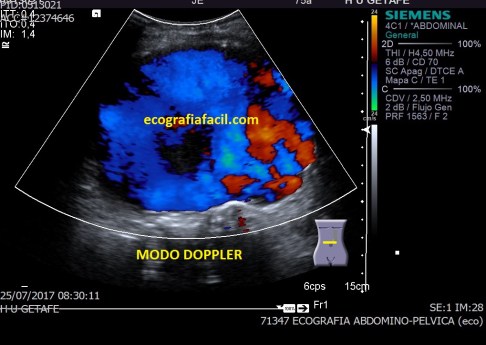

Después aplicamos el doppler, tanto el color como el modo angio donde observamos la vascularización del tumor, ojo a la escala que usemos, tiene que estar adaptada a la vascularización de la ecoestructura que estemos estudiando para ver la correctamente, de nada me sirve poner el doppler si la escala no está bien ajustada ,es decir, demasiado alta o baja, de ese modo, las lecturas de flujos lentos o rápidos no serán estudiadas por mala técnica.

Si observas en el margen superior izquierdo de la imagen 3 y la imagen 4 vas a ver que la escala es baja (3,8 cm/sg), por tanto el flujo de la lesión sabemos que es baja. Si nosotros usamos una escala muy alta, no podríamos ver las imágenes que estás viendo, y como en esta imagen, en todas las imágenes de neoformaciones a las que te enfrentes en tu día a día.